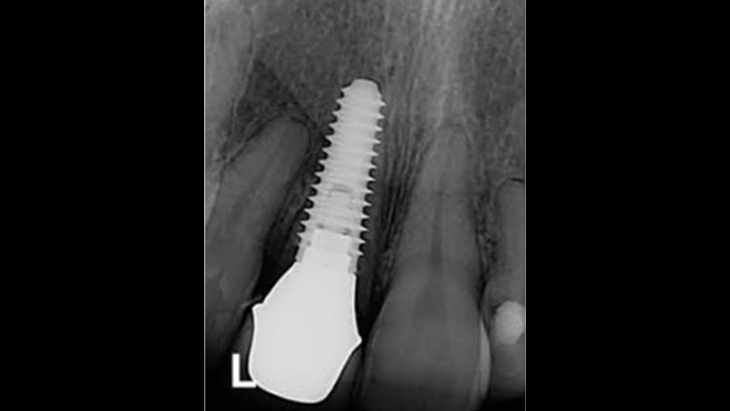

Clinical case: Bone filling into the bottom of deepest thread at 8.0mm AnyRidge fixture

- Courtesy of Dr. Kwang Bum Park -

Keywords

AnyRidge, Knifethread ,extraction socket, ,initial stability ,Allograft, ,osseointegratio ,Dr. Kwang Bum Park, , Mandibular, Single replacement, AnyRidge, Mega-oss,

Products used

Implant system-AnyRidge, Regeneration-Mega-Oss